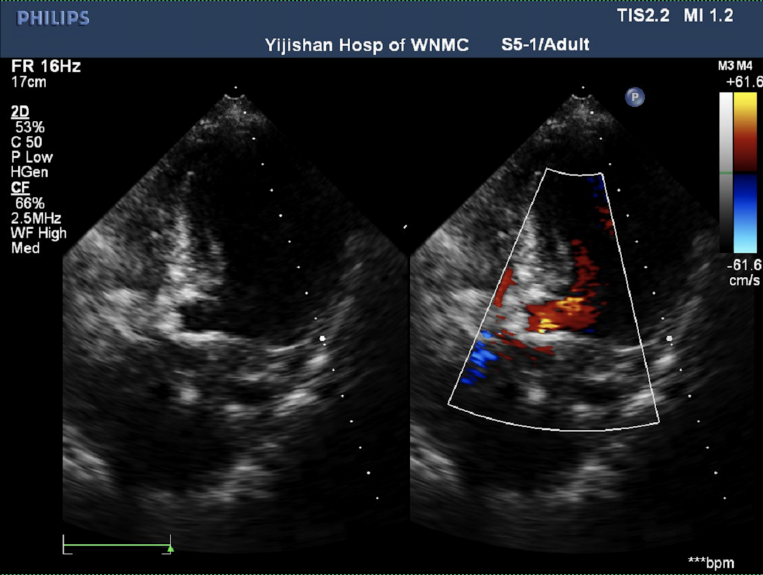

心脏超声

峰值流速4.88m/s,最高跨瓣压差95mmHg,平均跨瓣压差54mmHg,瓣口面积0.57cm²,左室射血分数EF 62%,左室舒张末期内径(LVD)44 mm。

诊断结果

主动脉瓣明显钙化(二叶瓣)伴重度狭窄,轻度返流;

左室壁弥漫性增厚,左室流出道加速不明显;

二尖瓣轻度反流;

心房增大;

升主动脉瘤样扩张、主肺动脉增宽。